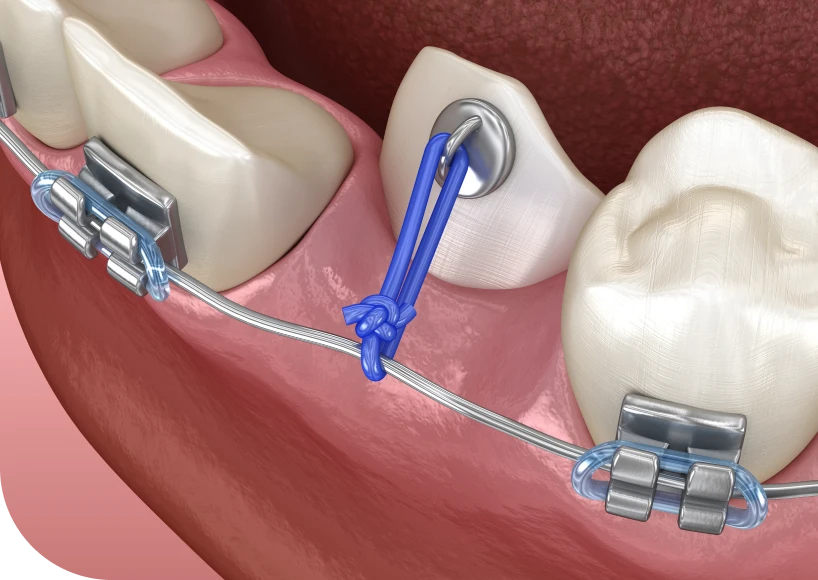

Le dégagement chirurgical consiste à libérer une dent bloquée pour permettre son redressement. L’intervention se réalise sous anesthésie locale ou générale, selon les cas. Elle se pratique au cabinet dentaire, dans un environnement adapté.

Étapes de la procédure

D’abord, le praticien incise la gencive pour accéder à la dent incluse. Ensuite, il peut retirer une fine couche d’os si la dent est entièrement enfouie. Puis, il pose parfois un dispositif de traction pour guider la dent vers sa place. Enfin, il referme la gencive par des sutures adaptées.